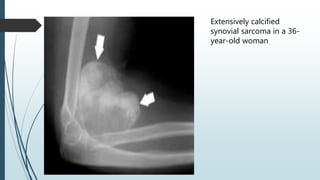

Extensively calcified

synovial sarcoma in a 36-

year-old woman